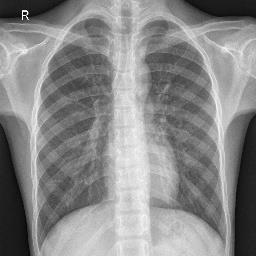

Pneumonia, a respiratory infection brought on by bacteria or viruses, affects a large number of people, especially in developing and impoverished countries where high levels of pollution, unclean living conditions, and overcrowding are frequently observed, along with insufficient medical infrastructure. Pleural effusion, a condition in which fluids fill the lung and complicate breathing, is brought on by pneumonia. Early detection of pneumonia is essential for ensuring curative care and boosting survival rates. The approach most usually used to diagnose pneumonia is chest X-ray imaging. The purpose of this work is to develop a method for the automatic diagnosis of bacterial and viral pneumonia in digital x-ray pictures. This article first presents the authors' technique, and then gives a comprehensive report on recent developments in the field of reliable diagnosis of pneumonia. In this study, here tuned a state-of-the-art deep convolutional neural network to classify plant diseases based on images and tested its performance. Deep learning architecture is compared empirically. VGG19, ResNet with 152v2, Resnext101, Seresnet152, Mobilenettv2, and DenseNet with 201 layers are among the architectures tested. Experiment data consists of two groups, sick and healthy X-ray pictures. To take appropriate action against plant diseases as soon as possible, rapid disease identification models are preferred. DenseNet201 has shown no overfitting or performance degradation in our experiments, and its accuracy tends to increase as the number of epochs increases. Further, DenseNet201 achieves state-of-the-art performance with a significantly a smaller number of parameters and within a reasonable computing time. This architecture outperforms the competition in terms of testing accuracy, scoring 95%. Each architecture was trained using Keras, using Theano as the backend.